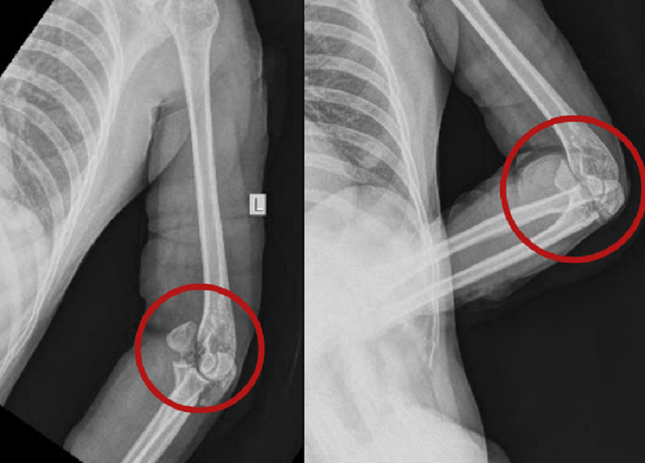

Theo BS Quang Nhật, khi tiếp nhận, qua thăm khám, chẩn đoán hình ảnh, các bác sĩ ghi nhận, vùng vai, cánh tay, cẳng tay, bàn tay cả hai bên của nạn nhân có nhiều vết thương dài và sâu, lộ gân, đứt cơ. Vùng khuỷu trái bị vết chém chí mạng gây gãy xương mỏm khuỷu, gãy xương lồi cầu trong xương cánh tay, lộ khớp khuỷu trái.

Trước tình trạng nguy kịch của chị T., bệnh viện đã kích hoạt báo động đỏ, huy động liên chuyên khoa thực hiện cuộc mổ cấp cứu. Trong quá trình phẫu thuật, các bác sĩ đã truyền máu bổ sung cho bệnh nhân, khâu lại toàn bộ gân cơ, dây thần kinh bị đứt.

Cuộc mổ cấp cứu đã giúp bệnh nhân vượt qua nguy kịch. Sau cuộc mổ thứ nhất, bệnh nhân được chăm sóc hậu phẫu ổn định. Các bác sĩ đã thực hiện cuộc mổ thứ hai kết hợp xương mỏm khuỷu, lồi cầu trong bằng nẹp vít cho bệnh nhân. Hiện sức khỏe của người bệnh đã bình phục tốt.